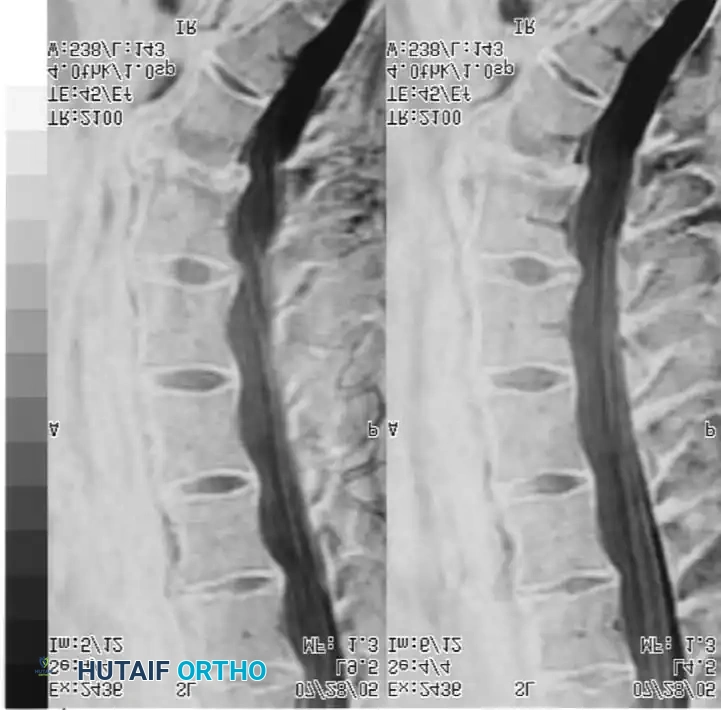

Magnetic Resonance Imaging (MRI) is the gold standard for evaluating disc hydration and morphology. In IDD, MRI typically reveals diminished water content in the nucleus pulposus, presenting as a "dark disc" on T2-weighted sagittal images. This may be accompanied by a loss of disc height and broad-based annular bulging.

Fig. 39-45 Fifty-one–year-old patient with chronic axial spine pain without neurological defi cits that did not respond to nonoperative treatments.

Fig. 39-45 MRI of a 51-year-old patient with chronic axial spine pain. Note the significant loss of signal intensity (dark disc) at the L5-S1 level on the T2-weighted sagittal image, indicative of severe desiccation and internal disc derangement.

It is imperative to understand that a dark disc on MRI has no diagnostic value in isolation. It must correlate perfectly with the clinical history and physical examination, as asymptomatic disc degeneration is highly prevalent in the general population.